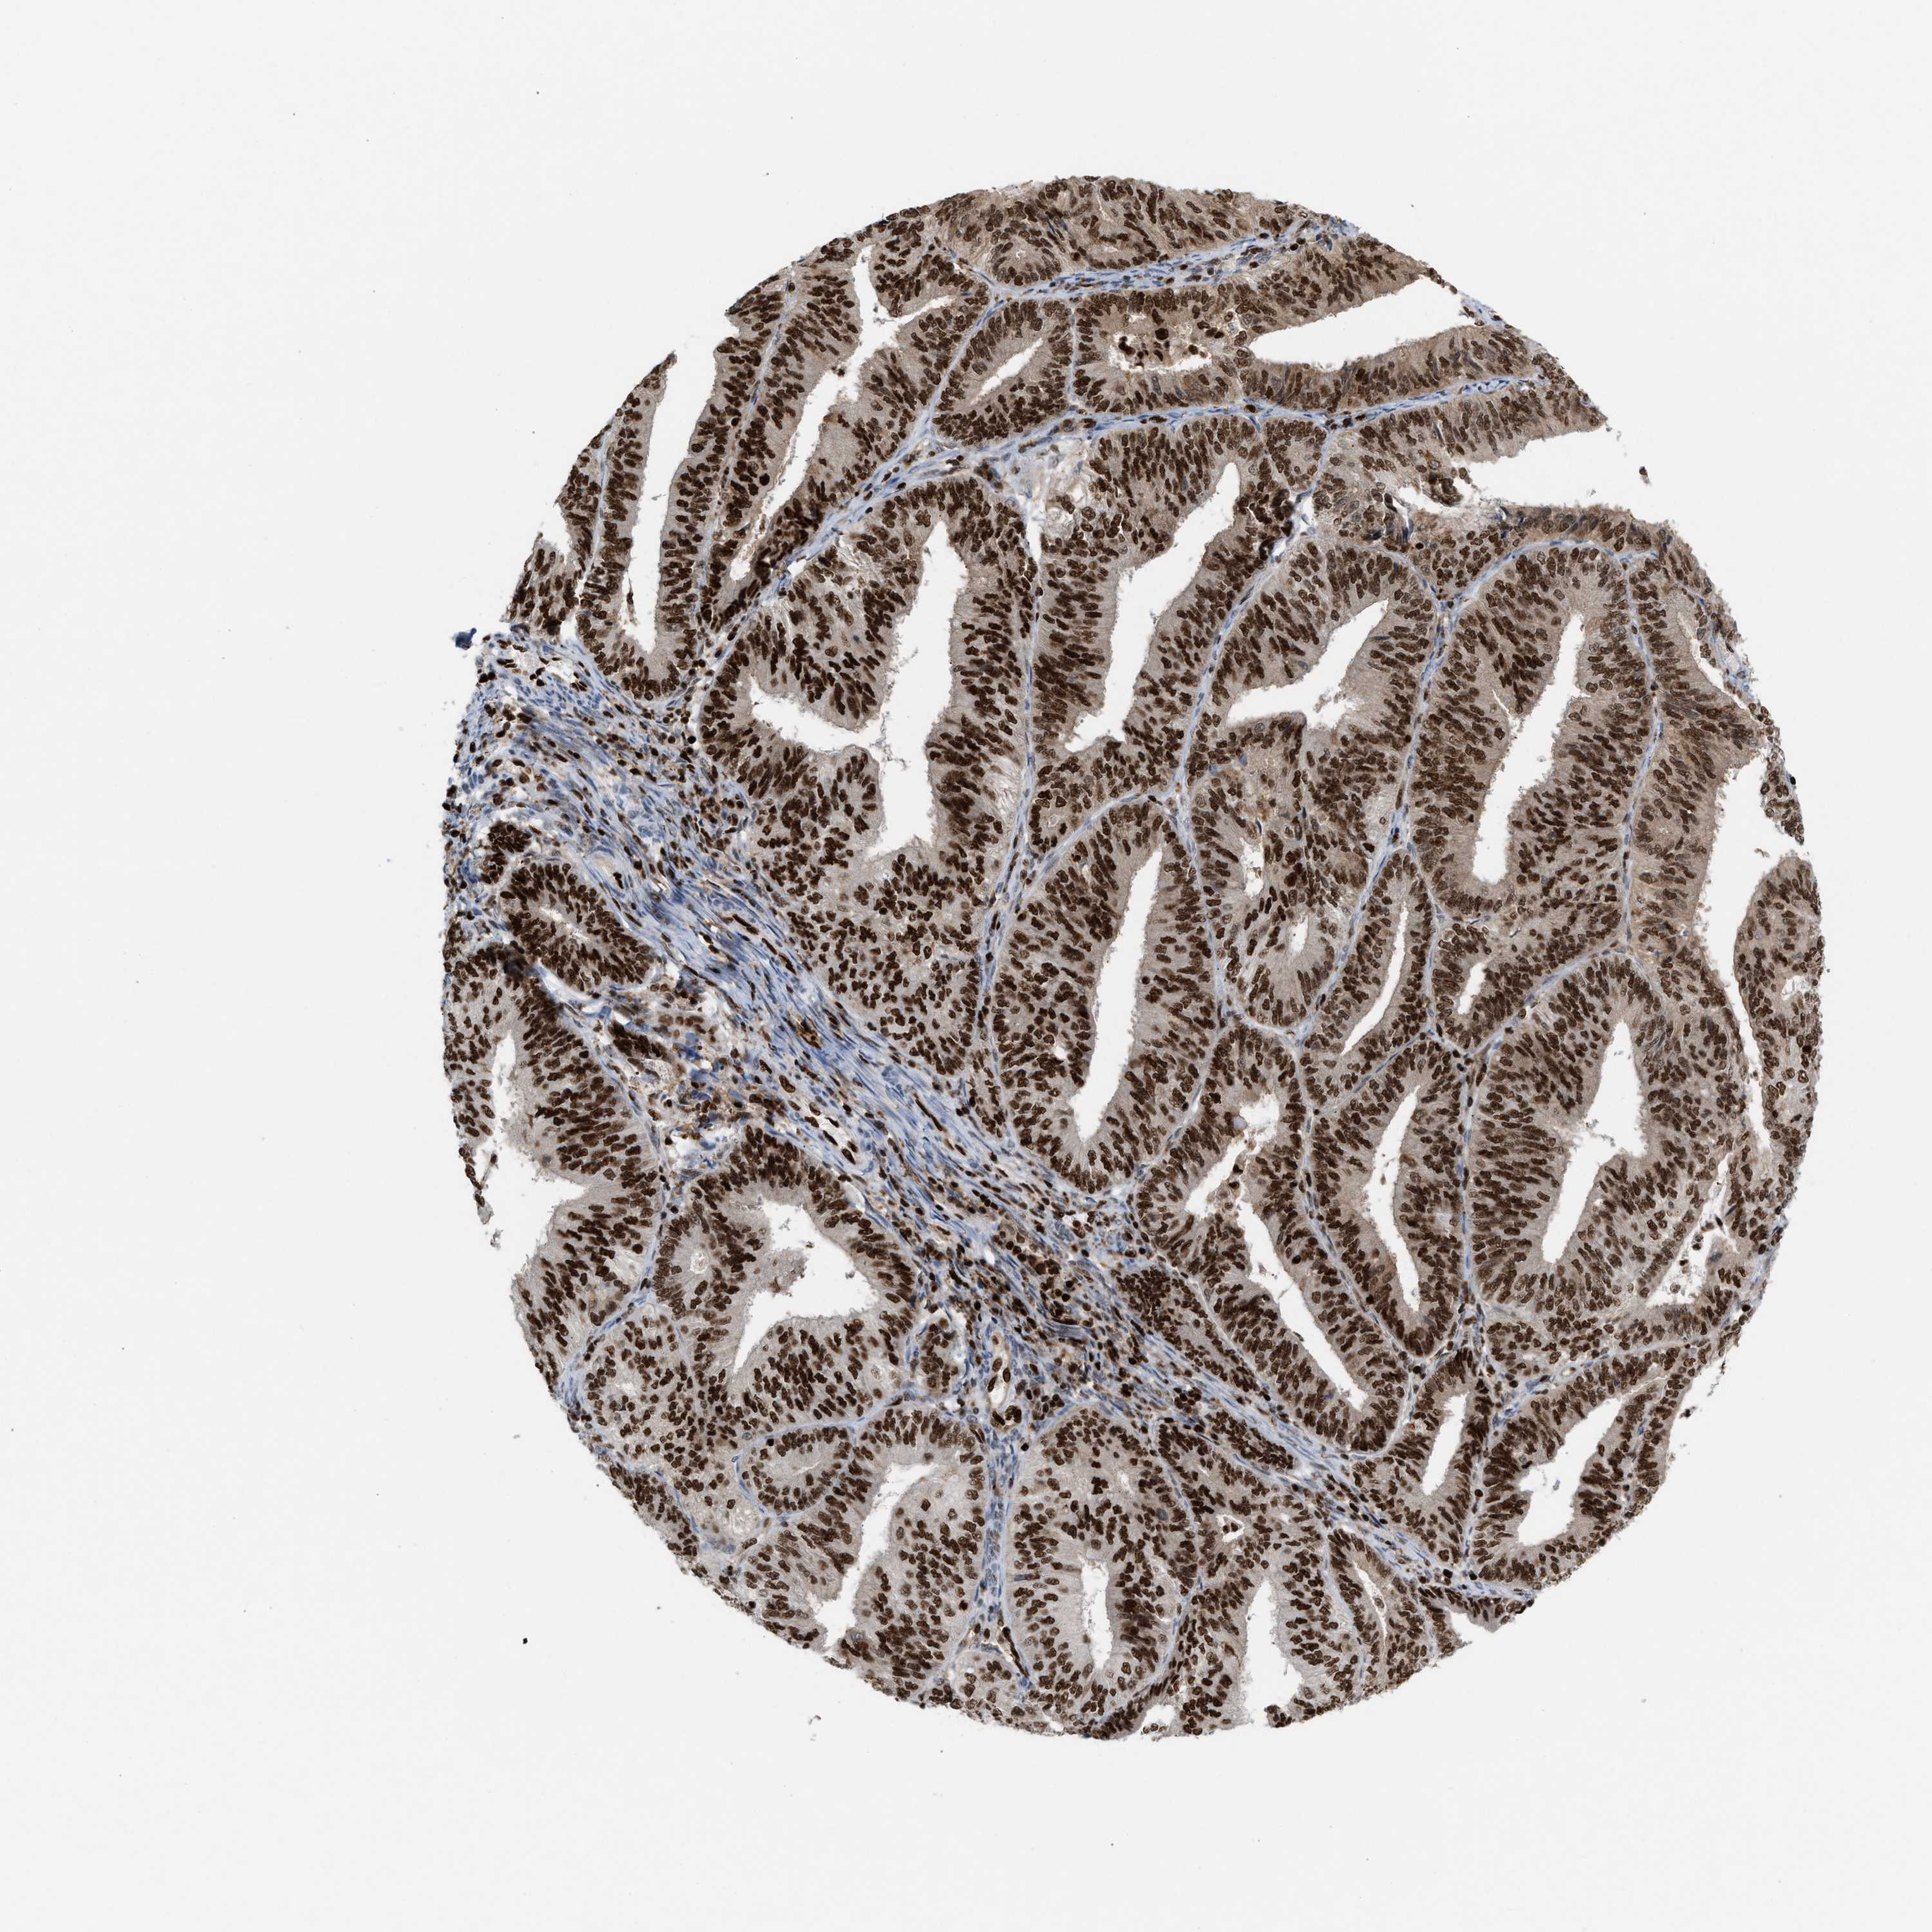

ENDOMETRIAL CANCER - Protein expressioni

A mouse-over function shows sample information and annotation data. Click on an image to view it in a full screen mode. Samples can be filtered based on level of antibody staining by selecting one or several of the following categories: high, medium, low and not detected. The assay and annotation is described here.

Note that samples used for immunohistochemistry by the Human Protein Atlas do not correspond to samples in the TCGA dataset.

Antibody stainingi

Antibody staining in the annotated cell types in the current human tissue is reported as not detected, low, medium, or high, based on conventional immunohistochemistry profiling in selected tissues. This score is based on the combination of the staining intensity and fraction of stained cells.

Each image is clickable and will lead to virtual microscopy that enables deeper exploration of all samples and also displays staining intensity scores, fraction scores and subcellular localization as well as patient and tissue information for each sample.

Antibody HPA022961

Antibody HPA024457

Staining

High

Medium

Low

Not detected

Intensity

Strong

Moderate

Weak

Negative

Quantity

>75%

75%-25%

<25%

None

Location

Nuclear

Cytoplasmic/membranous

Cytoplasmic/membranous,nuclear

Adenocarcinoma, NOS